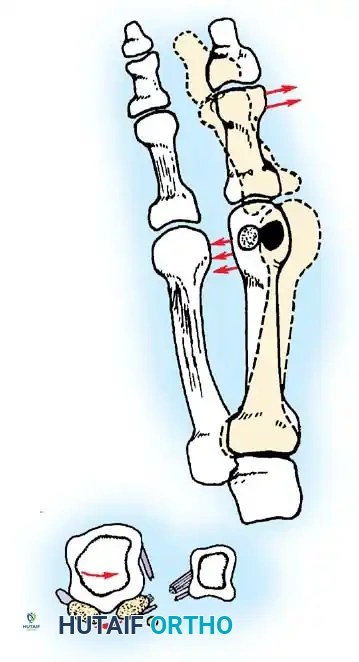

Keller Resection Arthroplasty The Keller procedure combines resection hemiarthroplasty of the fi rst metatarsophalangeal joint with removal of the medial eminence of the fi rst metatarsal (Fig. 78-28). Although removing the base of the proximal phalanx decompresses the joint and mobilizes the hallux, allowing marked correction of valgus, the varus of the fi rst metatarsal is not corrected, and maintaining correction of the valgus of the hallux is diffi cult. Other complications of the Keller procedure have been emphasized in the literature to such an extent (with neither the incidence nor the severity of such complications clearly documented) that the indications for this procedure have been limited severely. In our experience, however, complications are uncommon if patients are selected carefully. Modifi cations in the original technique also have allowed expansion of the indications for the Keller bunionectomy. Candidates for the Keller procedure are patients older than 50 years with moderate-to-severe hallux valgus (30 to 45 degrees); intermetatarsal angles of 13 degrees or less, indicating mild-to-moderate metatarsus primus varus; and pain over the medial eminence with any shoe worn, so the variety of shoes the patient can wear is severely limited. An incongruous fi rst metatarsophalangeal joint caused by

Fig. 78-26 Modifi ed McBride bunionectomy (DuVries; Mann). A, Medial capsule of second metatarsophalangeal joint is sutured to lateral capsule of fi rst metatarsophalangeal joint with interposition of released adductor hallucis. B, Medial capsular resection. C, Confi guration after capsular resection. D, After capsular imbrication, hallux should rest in neutral position or not exceed 5 degrees of varus. E, Postoperative dressing technique (Mann). ( E after Beverly Kessler; courtesy of LTI Medica and The Upjohn Company.) lateral subluxation of the phalanx on the metatarsal head, severe lateral displacement of the sesamoids, and any evidence of degenerative cartilage changes in the joint all are radiographic indications for the Keller procedure. Two modifi cations in technique can expand these indications, however, to include patients with more severe deformities (Fig. 78-29) (but not to include younger patients): fi bular sesamoidectomy and lateral displacement of the fi rst metatarsal. Using these modifi cations, Donley et al. obtained an average 18-degree correction of the metatarsophalangeal angle and an average 6-degree correction of the intermetatarsal angle in 38 patients (50 feet);

The following modifi cations of the Keller technique can expand the indications for use with more severe deformities.

LATERAL DISPLACEMENT OF THE FIRST METATARSAL

Fig. 78-31 Excision of fi bular sesamoid in modifi ed Keller procedure. With base of proximal phalanx removed and medial eminence excision, exposure of fi bular sesamoid is not as diffi cult from medial incision. A, Operative photograph showing elevation of fi rst metatarsal with strong two-tooth retractor and use of small osteotome to mobilize fi bular sesamoid and lateral capsuloligamentous (frequently contracted) structures. Osteotome is between metatarsal head and lateral sesamoid. When mobilization of fi bular sesamoid is complete, entire sesamoid is visible for excision. Note chondromalacia of tibial sesamoid articular surface medial to osteotome. B, Fibular sesamoid has been excised, and lateral capsular structures and conjoined tendon (in forceps) have been released. Neurovascular bundle to lateral side of hallux is adjacent to these structures. C, Diagrammatic representation of modifi ed Keller procedure. By excising fi bular sesamoid, valgus moment of conjoined tendon of fl exor hallucis brevis and adductor hallucis no longer pulls fl exor hallucis longus tendon laterally (carrying hallux with it) through capsulosesamoid plantar plate and pulley system. D, Metatarsal head must be lifted dorsally to excise fi bular sesamoid under direct vision. E, Note exposure of fi bular sesamoid after mobilization of metatarsal head. Continued

Presumably, the laterally displaced fi bular sesamoid, when pulled proximally by the lateral head of the relaxed fl exor hallucis brevis, pulls the fl exor hallucis longus laterally through the sesamoid apparatus, which encases it and contributes to recurrent hallux valgus. In addition, while reoperating after a failed Keller procedure, we observed a strong, linear, fi brous attachment of the fi bular sesamoid to the proximal phalangeal remnant (Fig. 78-32), which pulled the hallux into valgus when tension was applied to it. For these reasons, when the deformity is severe, the hallux and fi rst metatarsal maintain better alignment if excision of the fi bular sesamoid and lateral displacement of the metatarsal are added to the procedure. joint, lateral capsulotomy at the metatarsophalangeal joint, and lengthening of the extensor hallucis longus tendon. Hohmann recommended lateral displacement and plantar tilting of the distal fragment, following osteotomy at the metatarsal neck to correct hallux valgus. In 1945, a report by Mitchell et al. of 100 osteotomies gave the procedure his name. Since then, several authors have presented large retrospective reviews of the Mitchell operation to correct hallux valgus in adults and adolescents, with satisfactory results ranging from 74% to 94%. Gibson and Piggott described a peg-in-hole distal metatarsal osteotomy that differed from the Mitchell procedure in its use of a lateral plantar spike on the proximal fragment in place of the lateral spike on the distal fragment (as recommended by Mitchell). The nonunion rate has been negligible in all series of the Mitchell procedure, and recurrence of the deformity has been infrequent. The most troublesome complication has been metatarsalgia, attributable to dorsifl exion malunion of the distal fragment, excessive shortening of the metatarsal, or both (Fig. 78-33). In a long-term (average 21 years) follow-up study of 105 Mitchell procedures, Fokter, Podobnik, and Vengust found that the most common complication was recurrent hallux valgus with medial eminence pain. Their good-to-excellent results deteriorated from 97% at follow-up ranging from 2 to 11 years to 64% at follow-up ranging from 15 to 24 years, primarily because of recurrence of deformity with medial eminence pain. The use of a Kirschner wire for fi xation (instead of sutures) prevented malunion; all osteotomies healed in 6 weeks with only secondary displacement. Likewise, with the pegin-hole procedure, metatarsalgia has been the most common complication. Relief of pain, narrowing of the forefoot, and correction of the deformity have been achieved in most patients, however. A closing wedge osteotomy at the subcapital level of the fi rst metatarsal to correct valgus of the hallux also has its proponents. Although opponents emphasize that metatarsus primus varus is worsened, and recurrence of the valgus deformity of the great toe is likely, published series have not confi rmed this. Of 32 osteotomies reported by Peabody and 76 reported by Funk and Wells, no nonunions or signifi cant recurrences of the deformity were recorded. A popular osteotomy of the distal metatarsal is the chevron intracapsular osteotomy, which was described by Corless in 1976 as a modifi cation of the Mitchell procedure to correct the bunion associated with mild-to-moderate metatarsus primus varus. The procedure consists of two parts: (1) correction of metatarsus primus varus by a V shaped osteotomy in the sagittal plane through the metatarsal head and neck, followed by lateral shifting of the metatarsal head and trimming of the proximal fragment without internal fi xation (because of the inherent stability of the osteotomy) and (2) correction of the hallux valgus by suturing a previously raised fl ap of joint capsule into the abductor hallucis tendon. Several series of this osteotomy with adequate clinical follow-up have been published. Austin and Leventen reported, in 100 osteotomies randomly selected for analysis from a group of 1200, that no nonunions, osteonecrosis, or infections occurred. Hattrup and Johnson reported, in 225 feet (157 patients), that pain, shoe fi t, and cosmesis were improved in all but a few patients. Because their best results were in younger patients, the authors indicated that